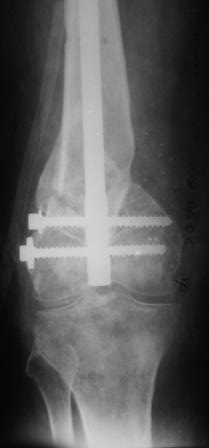

Уважаемые коллеги! Представляю на ваш суд ближйший результаты лечения.

На момент операции не было возможности запечатлеть увиденное, поэтому попытаюсь пересказать.

Первое что пришло в голову по аналогии очень похоже на асептический некроз головки бедра когда головку извлекают при эндопротезировании.Хрящ внутреннего мыщелка бедра был отслоен и изменен,сам мыщелок проминался под пальцем. От блокирования стяжкой отказались. Можно ли это расценить как асептический неркоз внутреннего мыщелка в результате первичной травмы?

Леонид Соломин писал о случае с пателлофеморальным синдесмозом(спасибо), но к сожалению сообщение пришло уже после операции.Прежде мы не встречались с подобным.Во время мобилизации после артролиза, отсечения интремедиуса попытались согнуть колено: хрящ надколенника остался на мыщелках бедра(!). В результате приняли решение удалить надколенник.

Раннее послеоперационное течение не очень спокойное- из раны было сукровичное отделяемое, но сейчас вроде идет на поправку(на фоне интенсивного лечения). В аттаче рентгенограммы.